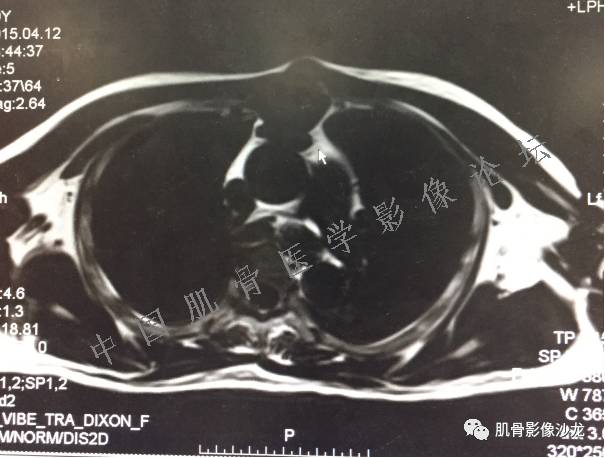

1、软骨肉瘤可以有膨胀性骨质破坏(病例3,4),可以有溶骨性骨质破坏(病例2),局部皮质因为破坏变薄,中断 ;

2、软骨基质T2WI高信号,软骨小叶分叶状,也就会出现高老师提到的骨内膜扇贝形压迹。一般认为骨内膜扇贝形压迹超过骨皮质厚度的2/3是软骨肉瘤在长管状骨的特征性表现。如上图。3、软组织肿块或肿胀;

4、 钙化,环形,弓形,边缘模糊 ;

5、增强后进行性延迟,不均匀分割状强化, 会强化的纤维间隔,软骨小叶不会强化,关于老师们说到的钙化,软骨肉瘤不一定会有钙化 。